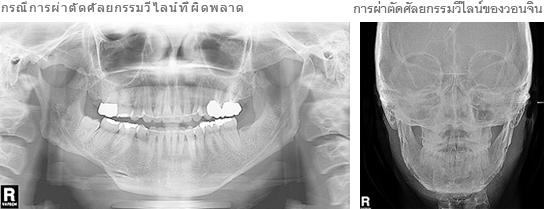

รูปภาพด้านบน (ทางด้านซ้าย) เป็นกรณีการผ่าตัดศัลยกรรมลดคางเหลี่ยมที่ผิดพลาด (การผ่าตัดศัลยกรรมวีไลน์) ตามภาพ จะเห็นว่ามีการตัดกระดูกเป็นรูปตัวอักษรวี ซึ่งอาจก่อให้เกิดปัญหาคางผิดรูป การผิดปกติทางใบหน้า หรือแม้แต่ปัญหาเส้นประสาทเสียหาย ตามเทคนิคการศัลยกรรมของโรงพยาบาลวอนจิน F.R.A. (Facial Ramus Angle) จะให้ผลการผ่าตัดคางเหลี่ยมที่ปลอดภัย และให้ผลรูปหน้าที่เรียวเล็ก